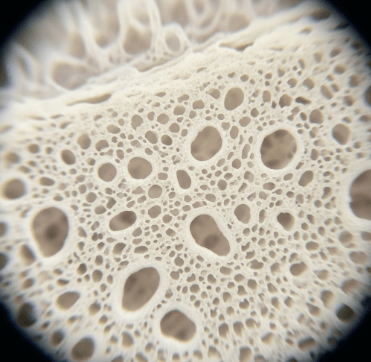

골다공증은 뼈에 구멍이 많이 생긴 것처럼 뼈가 약해져서 작은 충격에도 쉽게 골절되는 질환입니다.

'침묵의 질병'이라 불릴 만큼 골절이 발생하기 전까지는 증상이 거의 없어요. 하지만 한 번 골절이 발생하면 회복이 어렵고, 연쇄 골절로 이어질 위험이 높습니다.